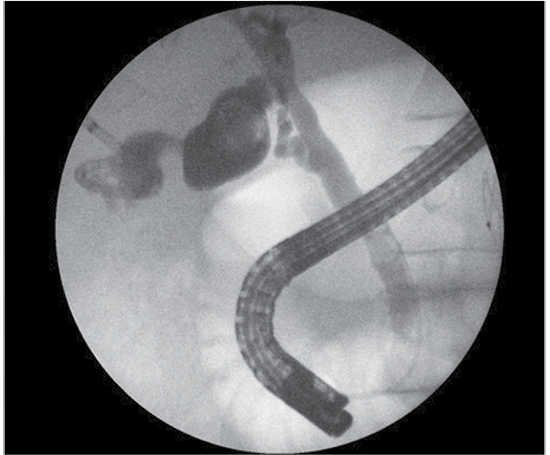

Figure 1. Endoscopic retrograde cholangiography demonstrates (A) an obstructed and dilated common bile duct with three about 1 cm gallstones, (B) a contrast-filled gallbladder with another large gallstone, and (C) a cholecystostomy drain

Four months later, the patient arrived as scheduled for operative treatment. At admission, cholangiography was performed through a cholecystostomy tube. During the procedure, gallstones were detected in the common bile duct. For this reason, it was decided to do endoscopic retrograde cholangiography and litectomy the next day (Figure 1).